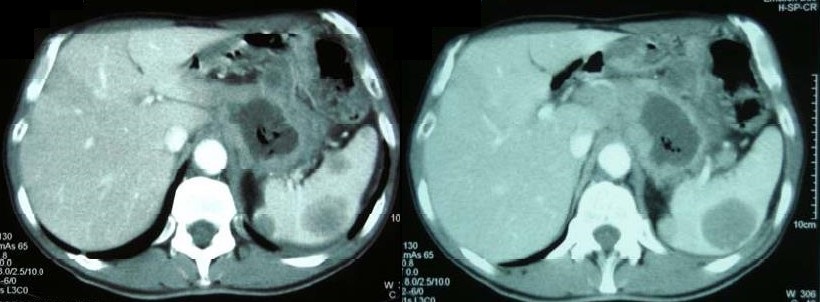

El paciente tiene una evolución inicial satisfactoria bajo tratamiento médico con inhibidores de la bomba de protones y antiácidos, sin recidiva del sangrado. Ante la posibilidad de estar frente a un cáncer gástrico por las características de la lesión en la endoscopía, se solicita una tomografía tóraco-abdominal que muestra pequeños nódulos pulmonares bilaterales y una extensa masa centroabdominal heterogénea y de centro hipodenso, en relación con la curvatura menor gástrica. Además el hígado presenta dos lesiones sólidas menores a 10mm en segmentos VI y VII, hay lesiones hipodensas múltiples en bazo de aspecto secundario y se observan gruesas adenomegalias retroperitoneales periaórticas e intercavoaórticas (ver imagen 2).

Imagen 2: Imágenes de la tomografía computerizada en la que se observa el extenso proceso que infiltra la curvatura menor gástrica y se extiende al retroperitoneo, así como las imágenes nodulares hipodensas esplénicas.

La Tomografía Computarizada de abdomen puede mostrar la presencia de un proceso infiltrante de aspecto neoplásico, con zonas hipodensas por necrosis o abscesificación, y conglomerados ganglionares retroperitoneales, como ocurrió en el paciente que estamos presentando, llevando al diagnóstico erróneo de probable cáncer. Esto se debe al comportamiento agresivo en lo local que la enfermedad puede adoptar en algunos pacientes, sobre todo inmunodeprimidos, infiltrando las paredes del órgano y tejidos adyacentes (1,4,5).